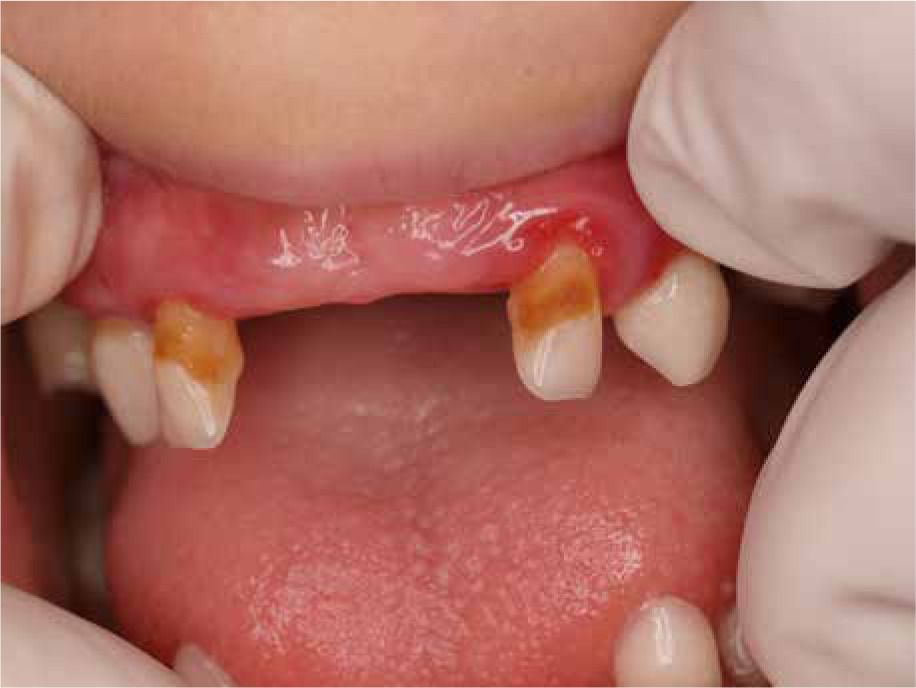

When the patient was 10, the exposure of two-thirds of palatal roots and third-degree loosening of teeth were observed (Fig. 3). A panoramic radiograph picture was taken (Fig. 4), which revealed complete absence of the bone base in all permanent first molars. Teeth 16 and 26 were qualified for extraction, which was performed in an outpatient setting under local anesthesia and antibiotic treatment (clindamycin, 10 mg/kg/dose). The obtained material from granulomatous lesions was submitted for histopathological examination, the results of which indicated non-specific inflammatory granulation tissue.

The next year, tartar deposits in the incisors of the mandible and gingivitis were discovered, and the mandibular first molars and central incisors showed signs of second-degree loosening. The patient was recommended to continue conservative treatment and undergo removal of the tartar deposits under antibiotic treatment (amoxicillin with clavulanic acid, 2 doses of 30 mg/kg with an interval of 12 hours, given at home). A few months later (Fig. 5), examination revealed intensified inflammation around tooth 36 with its roots halfway exposed, as well as looseness of teeth 32-42. Extraction of tooth 36 was performed under local anesthesia in an outpatient setting and covered with intravenous antibiotic (amoxicillin with clavulanic acid 30 mg/kg/dose).